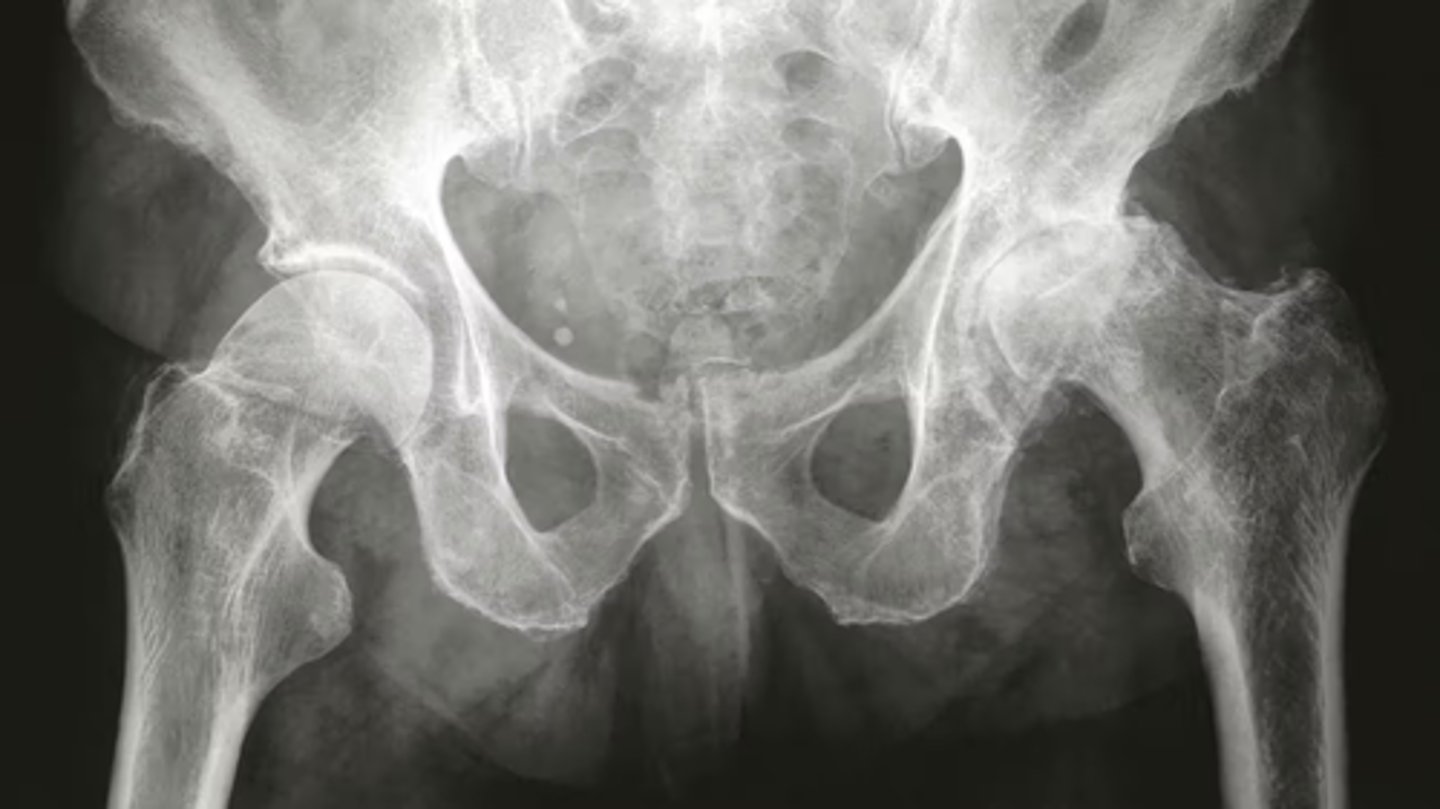

OA on left hip

radiograph "LOSS"

a. Loss of joint space

b. Osteophytes - spurs of bone

c. Subarticular sclerosis

Increased density of bone on joint line

d. Subchondral cysts

Small fluid filled holes in bone on the joint line